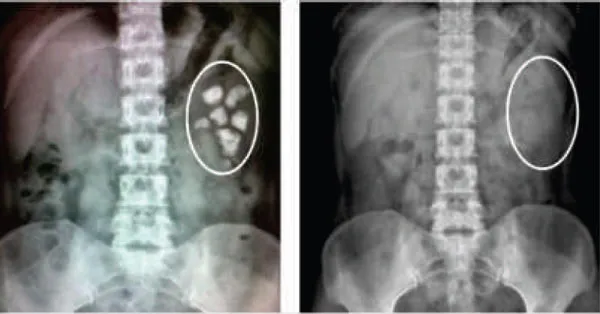

Ảnh minh họa

Sau khi sỏi hình thành, to dần, nhiều dần, dẫn đến viêm đường tiết niệu, đến giai đoạn cuối làm hoại tử thận, xơ gan và biến chứng, đây là quá trình phát triển dần của bệnh, không nhất thiết phải phẫu thuật, tán sỏi, nên dùng thuốc điều trị triệt để kịp thời.

Bài thuốc Phật Môn này sau khi đưa vào nước ta, đã có trên 20.000 người bệnh nghiệm chứng: sau 1 tháng sỏi to biến nhỏ, sỏi nhỏ tan hết; dùng 2-3 liệu trình các loại sỏi trong cơ thể dần dần tan và được đẩy ra ngoài. (Chú ý: Sỏi mật dùng thêm khoảng 1 liệu trình).